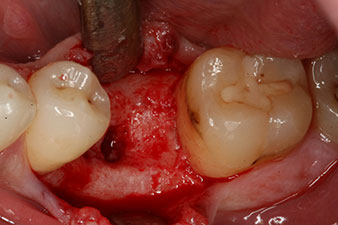

peri-implant bone deficit

Fig. 5: The peri-implant bone deficit must be compensated with autogenous bone chips to restore the peri-implant tissue contour.